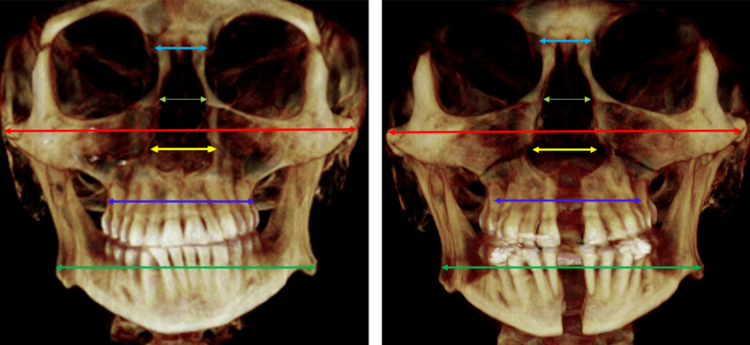

Пиздец, а если сначала сделать пикрил - расширение челюстей дистракторами, а уже потом с расширенной челюстную (костной) дугой и без (!) удаления зубов как при брекетах, уже ставить брекеты на это все - высокие риски зубных пиздецом?

Аноним 09/04/25 Срд 21:07:00 1614394 241

Чё за костные дуги? Брекетами нельзя расширить челюсть. Я делал расширение вч дистрактором и потом ещё сегментацию на три части, ничего не отвалилось. Ну брекеты тоже были. Из побочек в области клыка у губы изменилась чувстветельность.

Аноним 09/04/25 Срд 23:41:32 1614422 243

>>1614407

>Чё за костные дуги?

Ну кости под деснами я так назвал ненаучно, те, что по опасениям многих от брекетов рецессируются

>Брекетами нельзя расширить челюсть

Я потому про дистракцию пикрил и упомянул

>Я делал расширение вч дистрактором и потом ещё сегментацию на три части, ничего не отвалилось

Найс, какие улучшения заметил по здоровью (дыхание, жевание, состояние ВНЧС мб) и внешке после всего?